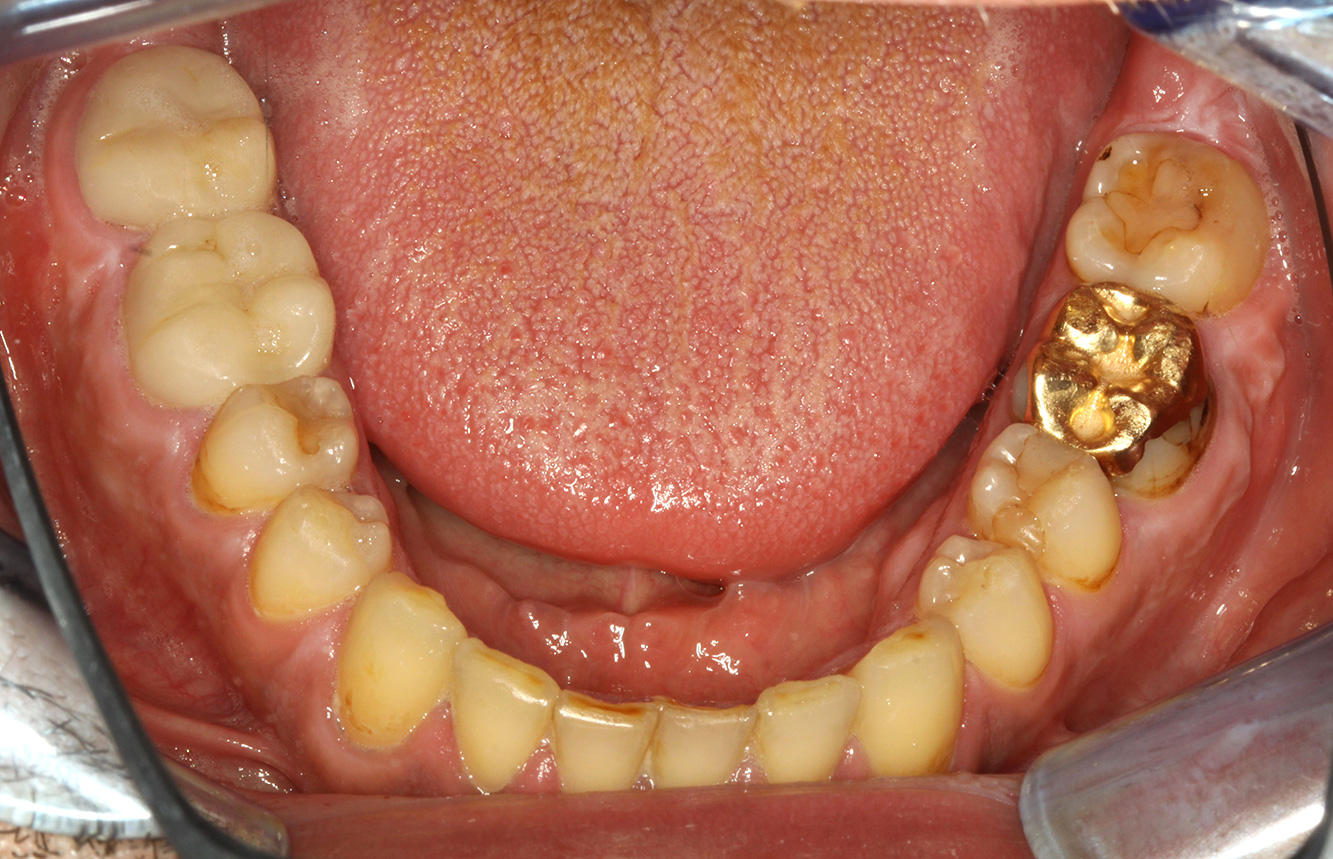

Der Patient ist 39 Jahre mit Z.n. Herzklappenersatz wegen Klappenfehlers und Endokarditis. Als Antikoagulans (Gerinnungshemmer) wird regelmäßig ASS 100 eingenommen. Aus dem Bereich Lebensstil ist die Ernährungsweise als kariesfördernd einzustufen, da mit hoher Regelmäßigkeit zuckerhaltige Lebensmittel sowie sechs bis sieben Mahlzeiten täglich verzehrt werden. Die Mundgesundheit des Patienten zeigt ein mittleres Kariesrisiko mit aktiven Läsionen. Das Parodontitisrisiko ist niedrig, es besteht eine Gingivitis. Es ergeben sich folgende Empfehlungen für die Prophylaxebehandlung.